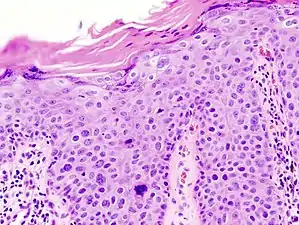

Histopathologically, the epidermis in cSCC in situ (Bowen's disease) will show hyperkeratosis and parakeratosis. There will also be marked acanthosis with elongation and thickening of the rete ridges. These changes will overly keratinocytic cells which are often highly atypical and may in fact have a more unusual appearance than invasive cSCC. The atypia spans the full thickness of the epidermis, with the keratinocytes demonstrating intense mitotic activity, pleomorphism, and greatly enlarged nuclei. They will also show a loss of maturity and polarity, giving the epidermis a disordered or "windblown" appearance.

Two types of multinucleated cells may be seen: the first will present as a multinucleated giant cell, and the second will appear as a dyskeratotic cell engulfed in the cytoplasm of a keratinocyte. Occasionally, cells of the upper epidermis will undergo vacuolization, demonstrating an abundant and strongly eosinophilic cytoplasm. There may be a mild to moderate lymphohistiocytic infiltrate detected in the upper dermis.[12]

Histopathology of squamous-cell carcinoma in situ (black arrow), compared to normal skin, showing marked atypia.

Squamous-cell carcinoma in situ, showing prominent dyskeratosis and aberrant mitoses at all levels of the epidermis, along with marked parakeratosis.[12]